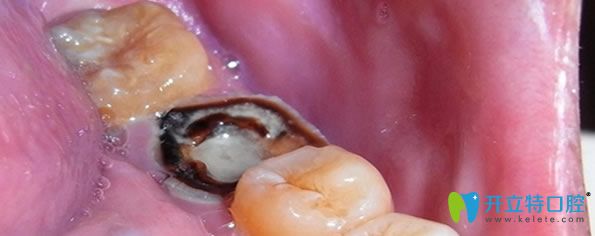

急性牙髓炎主要是細(xì)菌感染引起牙髓組織的急性炎癥,遇冷更加疼痛。急性牙髓炎發(fā)病急,疼痛劇烈,牙齦紅腫、化膿等癥狀,一般鎮(zhèn)痛藥物效果不明顯,遇到良心牙醫(yī)會(huì)保存活髓及患牙,利用開髓及藥物來(lái)緩解疼痛,服用消炎藥兩到三天,疼痛緩解后,嚴(yán)重的牙髓炎可采取根管治療或者活髓切斷術(shù),能夠及時(shí)預(yù)防病情嚴(yán)重及擴(kuò)散。沒有保存價(jià)值的牙齒可拔掉。

急性牙髓炎治療方法